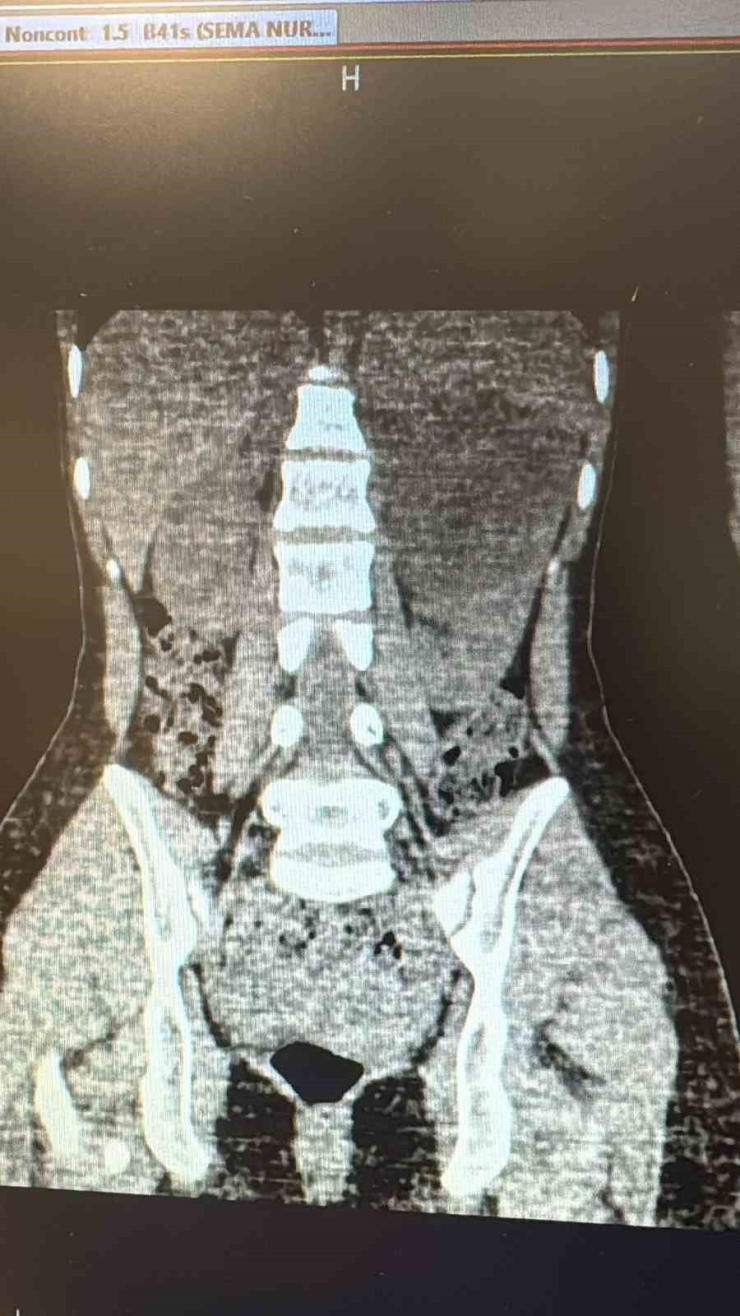

Şanlıurfa Viranşehir Devlet Hastanesi'nde, 18 yaşındaki bir hastanın sol böbreğinde tespit edilen yaklaşık 10 santimetre çapındaki kist, laparoskopik (kapalı) yöntemle başarıyla çıkarıldı.

Uzun süredir sol yan ağrısı şikâyeti bulunan kadın hasta, dış merkezde yapılan tetkiklerde sol böbrekten kaynaklanan, böbrek ve dalağı iterek komşu organlara yapışıklık gösteren büyük bir kist tespit edilmesi üzerine Viranşehir Devlet Hastanesi'ne sevk edildi. Hastanede yapılan değerlendirmelerin ardından kistin cerrahi yöntemle alınmasına karar verildi. Üroloji kliniğinde gerçekleştirilen operasyonda, 10 santimetre boyutundaki böbrek kisti laparoskopik yöntemle, 2 adet 5 milimetre ve 1 adet 10 milimetrelik kesi kullanılarak çıkarıldı. Böylece hasta, açık cerrahiye gerek kalmadan tedavi edildi. Ameliyat sonrası takiplerinde herhangi bir komplikasyon gelişmeyen hasta, sağlığına kavuşarak taburcu edildi.